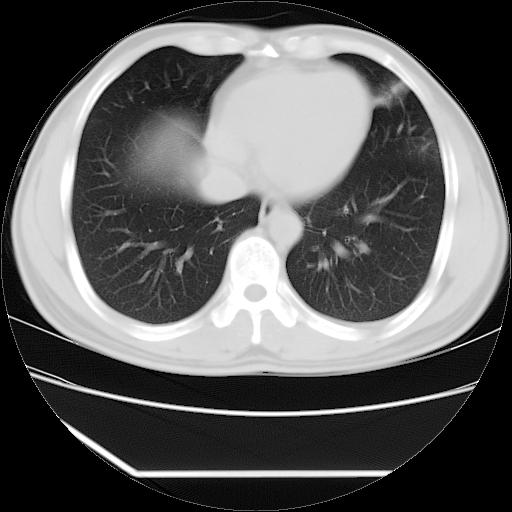

男,38岁,于2009年8月9日晚突发左侧胸痛,今x线提示左下肺阴影,为了明显确诊断,行ct检查,

血常规:嗜酸性细胞增高,单核细胞增高。

病灶发生在下叶,密度均匀,边缘模糊、毛糙,周围血管纹理增强扭曲改变,靠近胸膜处病灶胸膜反应明显。

支持考虑---球形肺炎。

左肺舌叶病变。主体病灶呈类圆形中心密度低,成液化趋势周边班片影分布

考虑肺脓肿

虽然实验室检查支持炎性病变,且病变内有坏死改变(中央呈大片状低密度影),但仍不能掉以轻心,鳞癌也可以有这种影像改变。